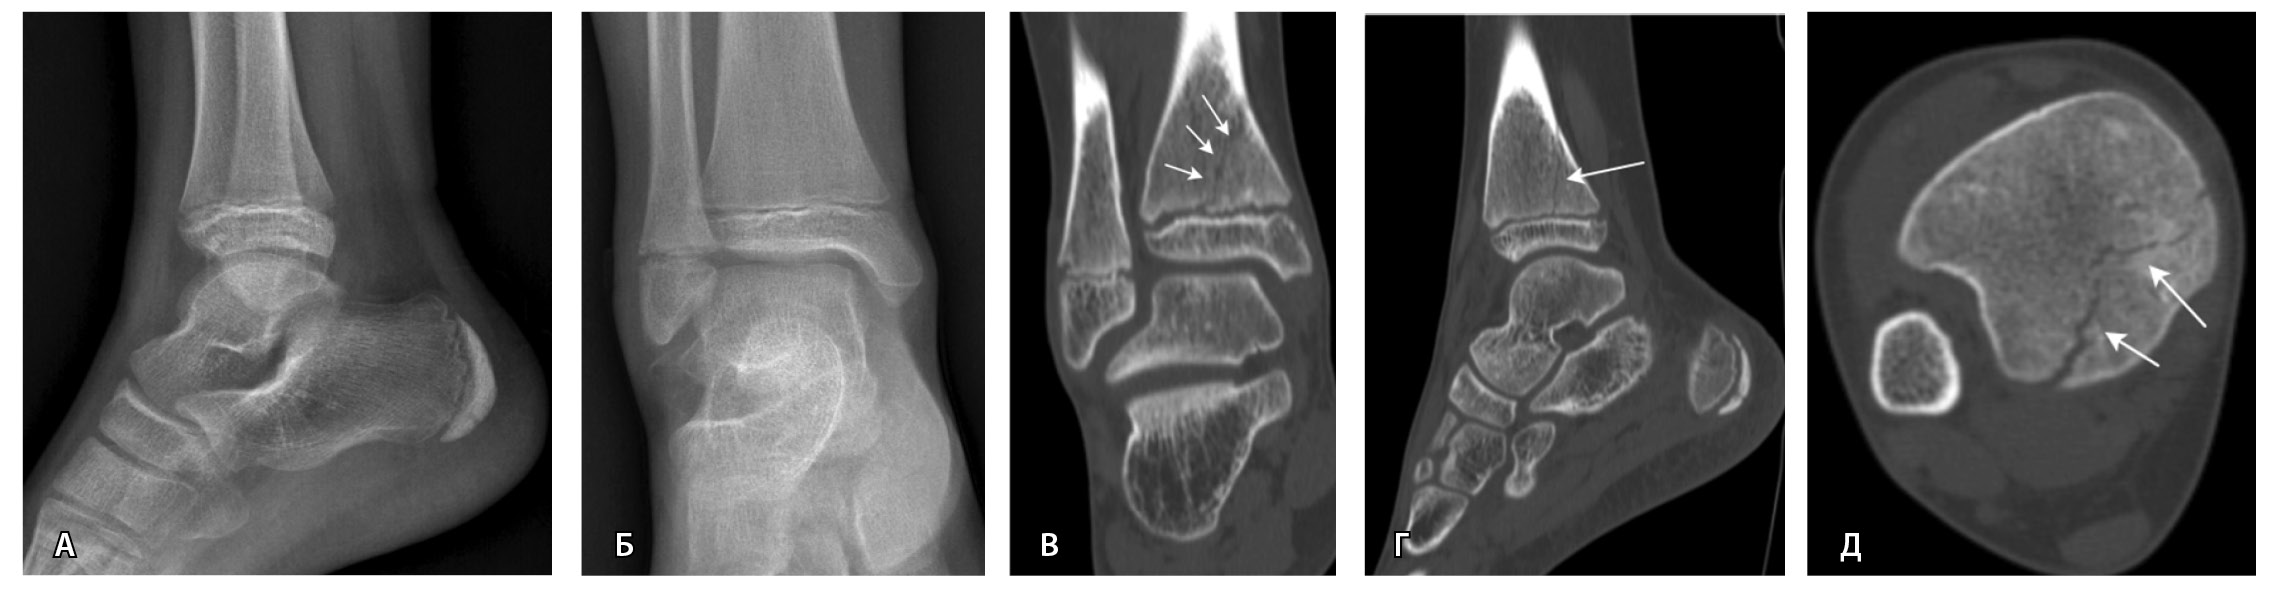

Рис. 2. Рентгеннегативный перелом дистального метадиафиза большеберцовой кости 2-го типа по Солтеру – Харрису (стрелки) у мальчика 11 лет: А, Б – рентгенография; В – компьютерная томография (КТ), корональная плоскость; Г – КТ, сагиттальная плоскость; Д – КТ, аксиальная плоскость

При переломах заднего края дистальной суставной поверхности большеберцовой кости («задней лодыжки») рентгенологическое исследование не всегда достаточно точно позволяет оценить наличие и размеры костных фрагментов, что зачастую обусловлено анатомической особенностью большеберцовой кости [18, 19]. Так, P.A. Bouche и соавт. выявляли переломы «задней лодыжки» в 1,5 раза чаще при помощи КТ (88,3%) в сравнении с рентгенографией (58,3%) [45].

Переломы таранной кости, в том числе с распространением линии перелома на подтаранный сустав, трудно обнаружить на рентгенограммах, однако КТ может помочь в их диагностике. M. Avci и соавт. выявили 30% чувствительность и 98% специфичность рентгенографии при переломах таранной кости [44]. J.D. Dale и соавт. установили, что рентгенография имеет более низкую чувствительность (78%) для обнаружения и локализации переломов таранной кости по сравнению с КТ (99%) [46]. Следует оценивать распространение линии перелома и ее близость к медиальной поверхности пяточной кости. Вовлечение пазухи предплюсны увеличивает риск развития остеонекроза и нестабильности в подтаранном суставе [23].